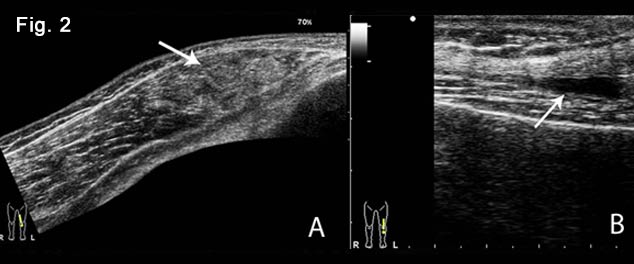

Figure 3: Longitudinal B-mode views of the right thigh.

A. Vastus intermedius and rectus femoris contusion. A gap filled with haematoma (thick arrow) is present in the vastus intermedius muscle throughout its width. There are small partial tears of the rectus femoris (arrow) at the site of traumatic skin retraction. Notice the diffuse subcutaneous edema.

B. Gray scale image showing the rupture of the peripheral part of the vastus intermedius with defect, filled with anechoic fluid from local haematoma. The torn muscle fragments are seen freely floating inside the haematoma, a sign referred to as the “bell clapper sign”.